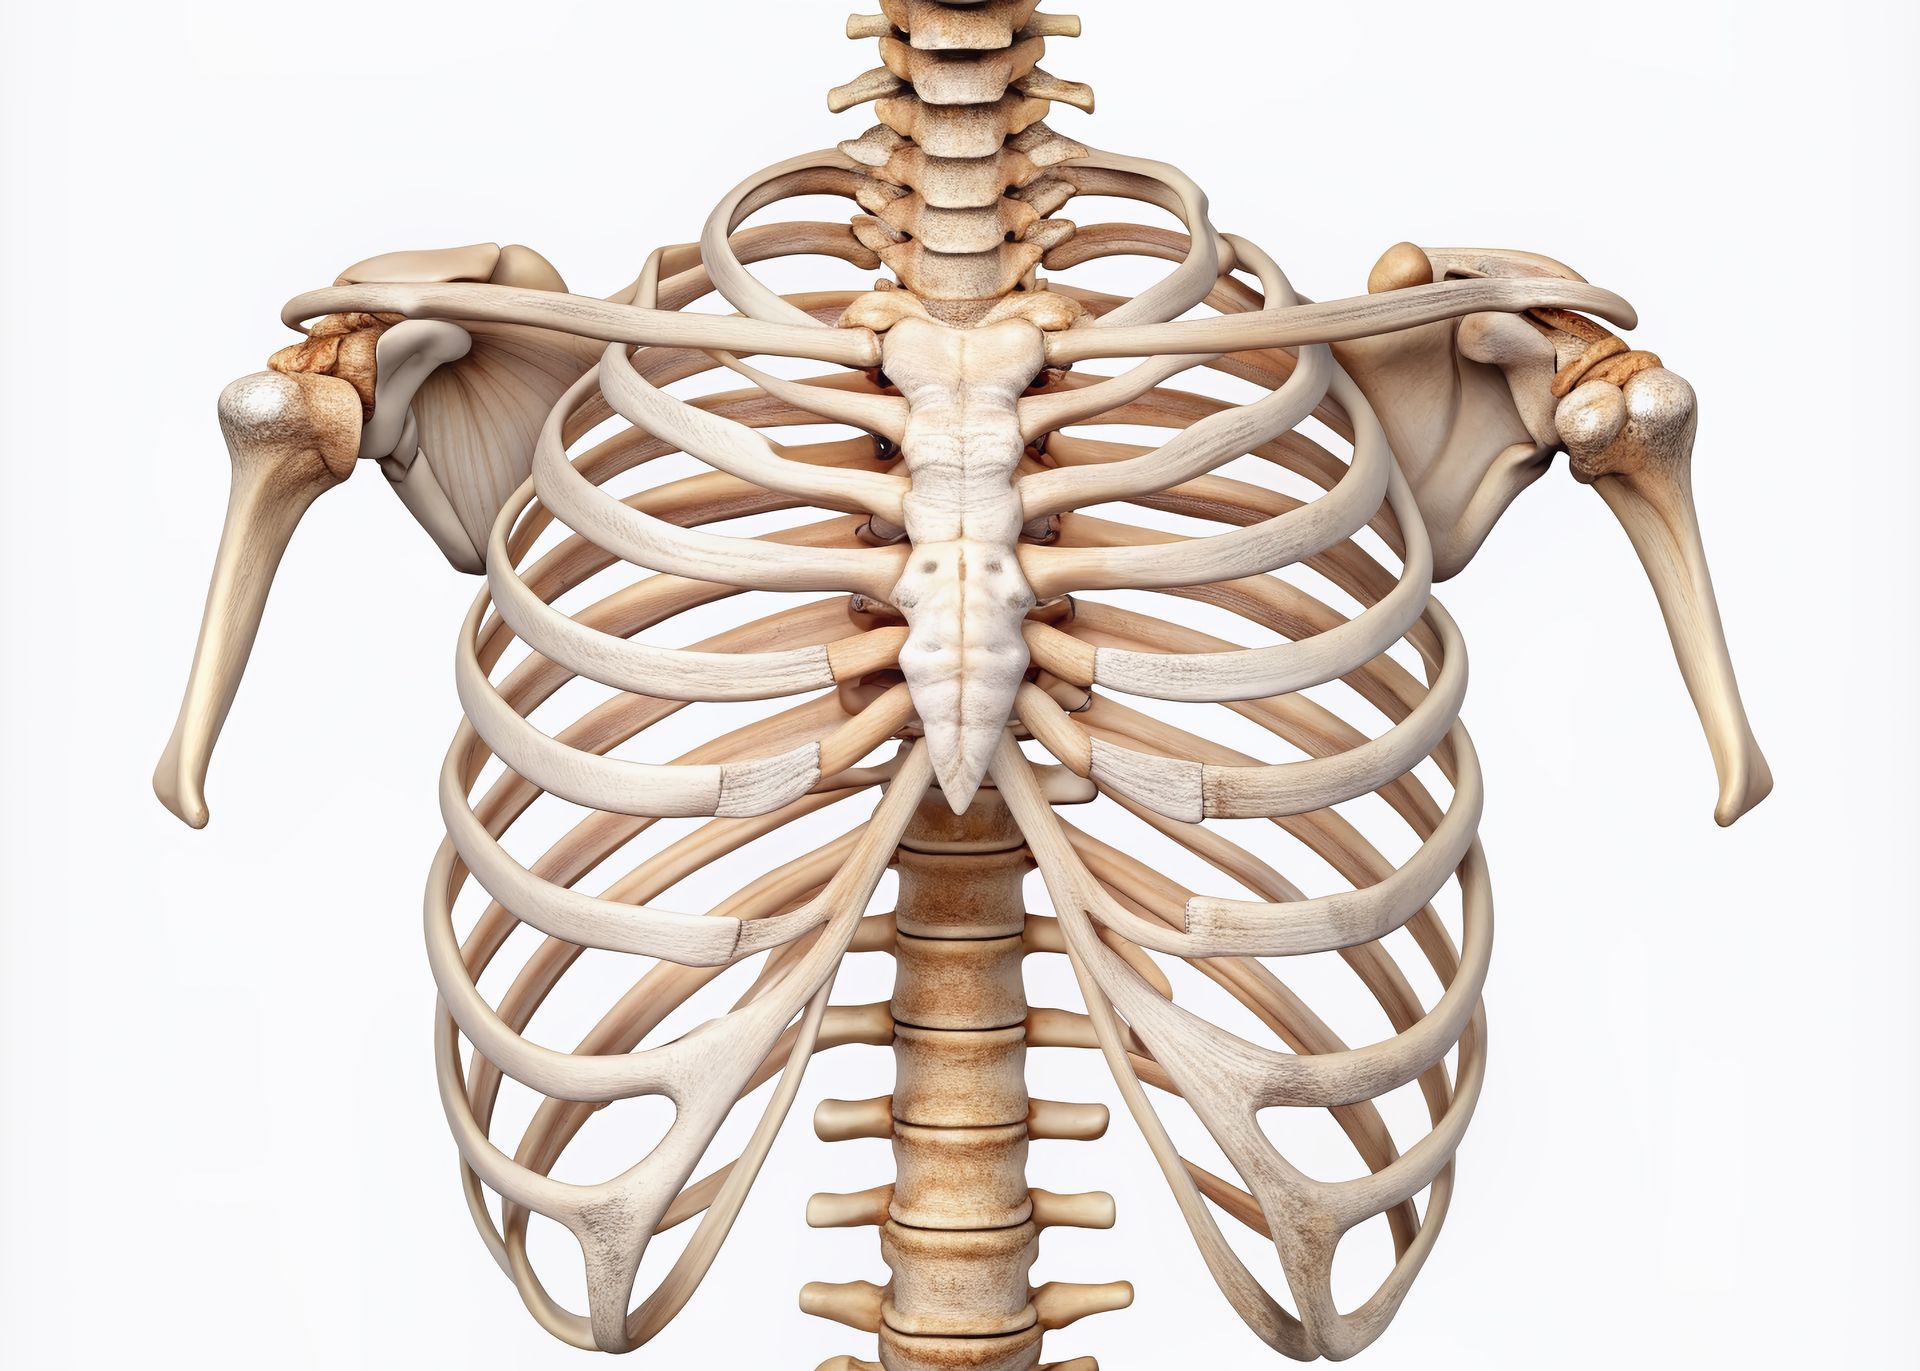

Cirurgião Torácico em Uberlândia - MG

O Dr. Vivalde Faria Lobato Neto é Cirurgião Torácico, referência em diagnósticos e tratamentos avançados para doenças pulmonares e torácicas. Com mais de 20 anos de experiência, combina cuidado humanizado, ética profissional e tecnologia de ponta para oferecer o que há de melhor aos seus pacientes.

Formado em Medicina pela Universidade Federal de Uberlândia, o Dr. Vivalde possui residências médicas em Cirurgia Geral e Cirurgia Torácica, além de pós-graduação em cirurgia torácica robótica e EBUS pelo renomado Hospital Israelita Albert Einstein. Especializado em técnicas modernas, como cirurgia robótica e ecobroncoscopia (EBUS), destaca-se pela precisão e segurança nos procedimentos realizados.

Especialização em Cirurgia Robótica Torácica, Ecobroncoscopia (EBUS) e planejamento cirúrgico com reconstrução 3D.